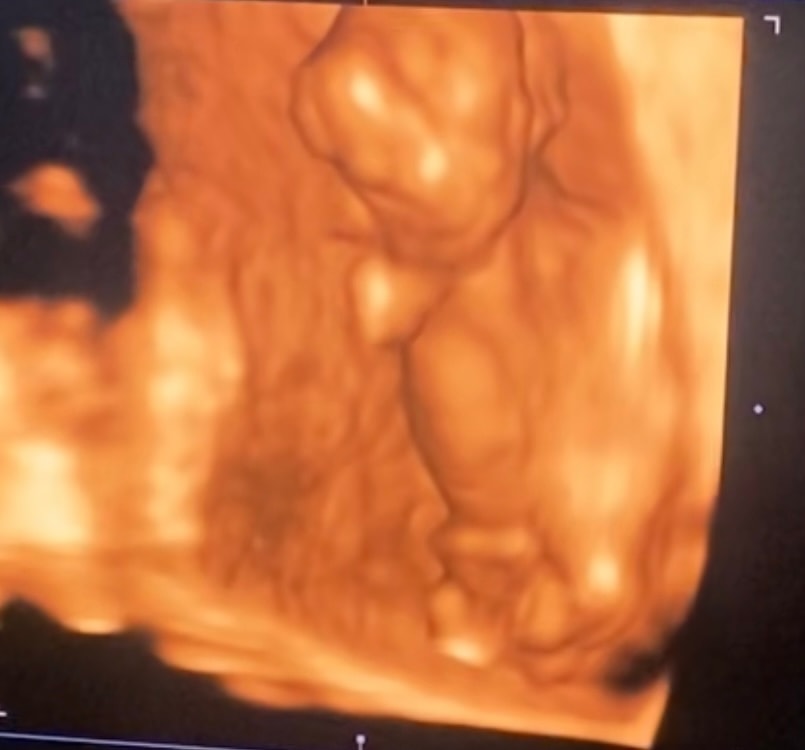

Малышка в 3 месяца отворачивается от груди и не спит 🙏